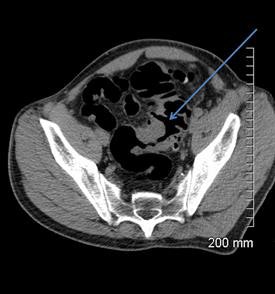

A 52-year-old man with a benign stricture, categorized as C4E1D4. The arrows highlight the smooth gradual transmural thickening within a diverticular laden sigmoid colon. Benign stricture was confirmed with surgical resection.